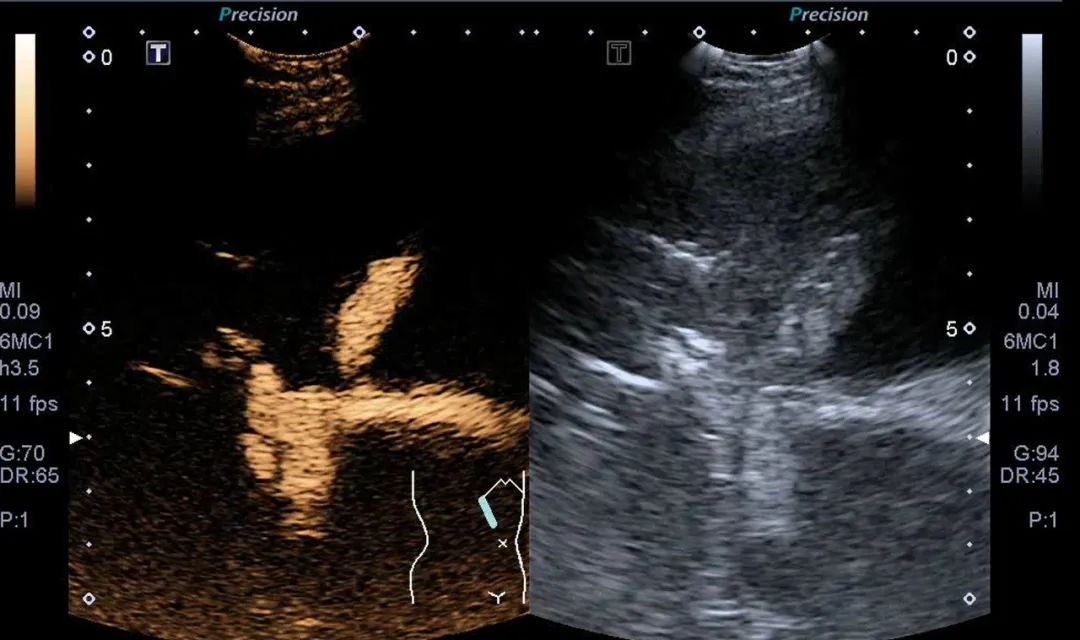

在征得患者和家属的同意后,手术正式开始了。手术当天,首先由医学超声科主任阮健秋带领的介入团队在超声引导下,用穿刺针把导丝置入胆管中。穿刺针在冯伯的上腹经皮经肝缓缓进入体内,在超声定位的护航下,穿刺针一点一点推进。大家全神贯注地盯着屏幕上闪烁的超声影像,根据多次跟消化科联合治疗的经验,团队顺利找到了术前预定的导丝放置位置,随后把导丝准确地放到十二指肠内,完成了关键的“开路”操作。

紧接着,消化内科李启祥主任及段雪辉副主任带领手术团队在内镜下使用圈套器在肠腔内将顺行的导丝成功“抓捕”,在下方导丝固定后,阮健秋主任团队马上沿导丝将顺行的导管送入肠腔内,同时把置换的黄斑马导丝轻松地放入到十二指肠内。不到半小时,PTCD与ERCP上下对接成功了!随后,在上方超声的实时引导及下方內镜持续监测下,李启祥主任团队以娴熟的技术,一气呵成地沿黄斑马导丝完成了胆道支架置入术。整个手术历时一个多小时,冯伯的生命通道终于打通了!